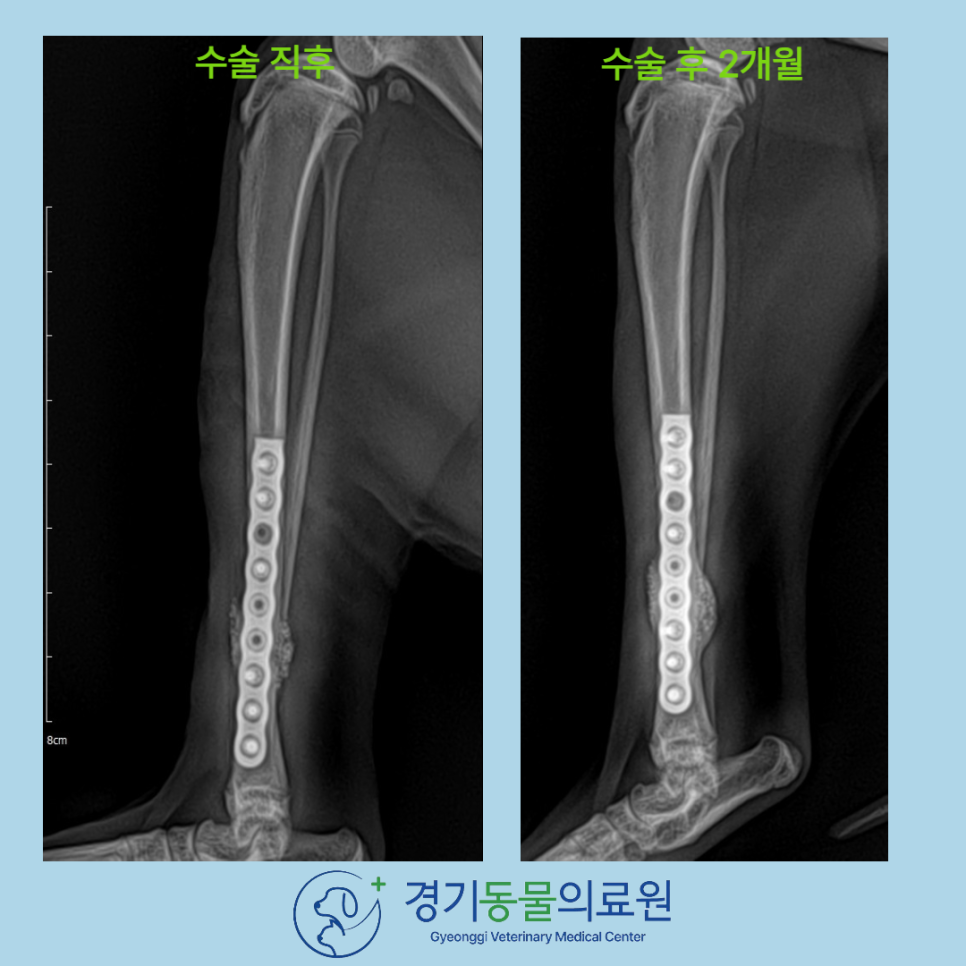

수술 후 X-ray 검사

경기동물의료원에서의 안전한 고양이 뒷다리 경골 골절 수술을 마친 후, X-ray 촬영을 통해 골절선이 보이지 않는 정도의 결과(화살표)를 확인할 수 있었습니다.

수술 후 이 냥이는 입원하며 통증 관리와 감염 예방 치료를 받았습니다.

수술 후 8주 차에 재진을 하려 내원했을때는 골유합 진행이 양호하였으며, 체중 부하 가능, 파행 증상 해소

가 확인되었습니다.